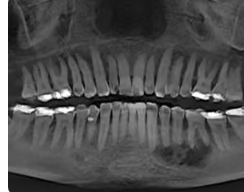

#30 see picture. Tooth responds normally to cold test. No pain on percussion.

What is this dental anomaly called?

Dens invagaintus